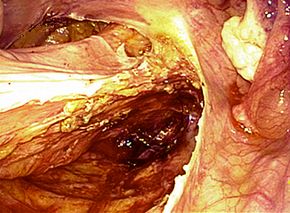

腹腔鏡下胆嚢摘出術の実際

全身麻酔をかけた状態で手術を行います。腹腔鏡下手術では腹部に4カ所の穴、単孔式

腹腔鏡下手術では1カ所の穴を開け、炭酸ガスをおなかの中に入れ、その穴から内視鏡

や手術鉗子を挿入し、画面を見ながら胆嚢を摘出する方法です。

単孔式腹腔鏡下胆嚢摘出術

腹腔鏡手術で胆嚢の摘出と総胆管結石の摘除を同時に行います。胆嚢摘出後、十二指腸

上部総胆管を切開し、胆道鏡を用いて直視下に胆石を除去します。

採石後は胆道鏡で結石遺残のないことを確認します。その後胆管切開部を腹腔鏡下に

体内で結紮縫合を行い、閉鎖します。